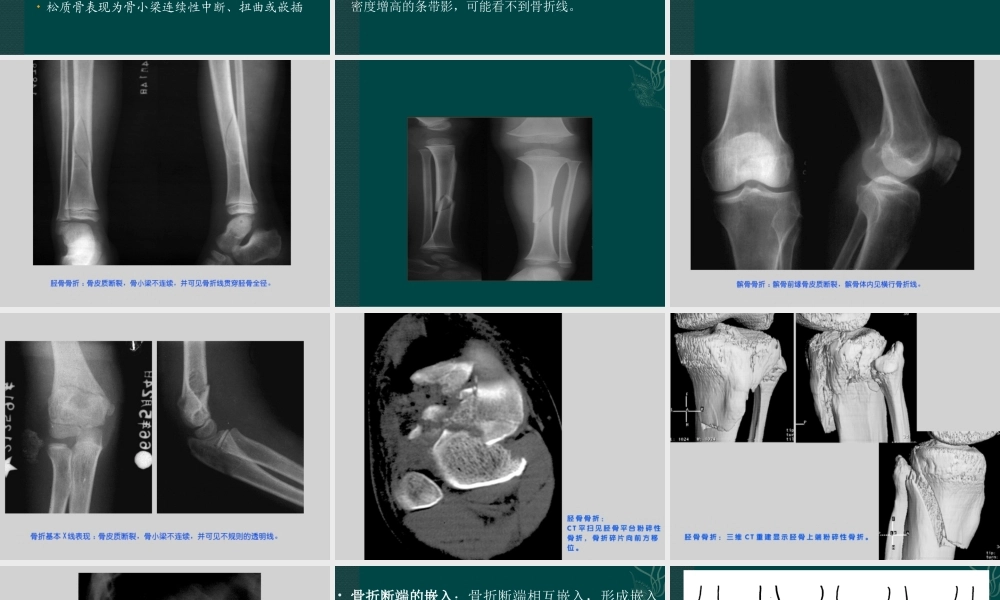

骨与关节创伤本节应了解、熟悉和掌握的知识点1.掌握骨骼、关节各种类型骨折的影像学表现2.熟悉骨关节损伤的CT和MRI影像学表现3.了解骨折愈合的病理组织学变化本节学习中的难点1.四肢和脊椎骨折的类型、判断骨折移位的标准及儿童骨折的特点,认识和掌握这些基本病变的X线表现对疾病诊断是重要的2.各种检查方法的成像原理及临床应用骨与关节创伤是常见病,影像学检查是主要手段X线平片是最简便有效而常用的方法MRI可直接显示软组织CT适于检查复杂结构3.1骨骼的创伤影像学检查目的:有无骨折或肌腱韧带断裂;了解骨折错位情况;需要时可在透视下行复位治疗;复位后拍片,了解复位情况;定期复查观察愈合情况和有无并发症;轻微外伤引起的骨折,应判断有无病理骨折;了解骨折是否累及关节;了解关节是否有脱位和关节软骨损伤(一)骨折总论骨组织的连续性中断称为骨折X线片上呈不规则的透明线称为骨折线骨皮质显示清楚松质骨表现为骨小梁连续性中断、扭曲或嵌插骨折以长骨和脊椎骨常见(1)长骨骨折定义:是骨或软骨结构发生断裂,骨的连续性中断,骨骺分离也属骨折。影像学表现基本X线表现:骨多为不整齐的断裂,X线上呈不规则透亮线,即骨折线,于皮质显示清楚整齐,在骨松质表现为骨小梁紊乱、扭曲、错位。严重骨折可使骨变形。嵌入性或压缩性骨折骨小梁紊乱,可局限出现密度增高的条带影,可能看不到骨折线。骨折的类型:根据骨折的程度可分为完全性和不完全性;根据骨折线的走向和形态,分为横行、斜行、螺旋形。复杂骨折的又可按骨折线形状分为T型、Y型等。根据骨碎片情况可分为撕脱性、嵌入性和粉碎性骨折。骨折的对位和对线关系:完全性骨折,要注意确定骨折断端的移位。骨折可发生内外、前后的移位,上下断端亦可相互重叠或分离。骨折端可以成角和旋转移位。骨折断端内外、前后和上下移位称为对位不良,而成角移位称为对线不良。骨折断端的嵌入:骨折断端相互嵌入,形成嵌入性骨折。X线片上并不显示透明的骨折线,表现为条带状密度增高影,系因相互嵌入的骨折端重叠所致。嵌入性骨折可引起骨骼的缩短与变形,移位不明显。嵌入骨折以股骨颈部多见。儿童骨折的特点:骺离骨折—骨折发生在儿童长骨,由于骨骺尚未与干骺端结合,外力可经过骺板达干骺端而引起骨骺分离。X线上只显示为骺线增宽或骺与干骺端对位异常。青枝骨折—在儿童,骨胳柔韧性较大,外力不易使骨质完全断裂,仅表现为局部骨皮质和骨小梁的扭曲,...